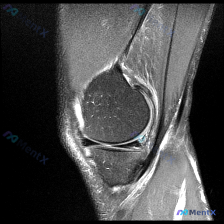

遇到一个挺典型的「临床-影像不匹配」的病例,整理出来和大家聊聊思路。 病例核心信息 问题:临床怀疑存在半月板异常,仅提供单张膝关节MRI-T2序列矢状位影像,请给出影像判断和分析。 影像所见整理 这张影像的情况是: 1. 骨结构:股骨远端、胫骨近端、髌骨皮质轮廓完整,骨髓信号均匀,没有骨折、骨挫伤、...